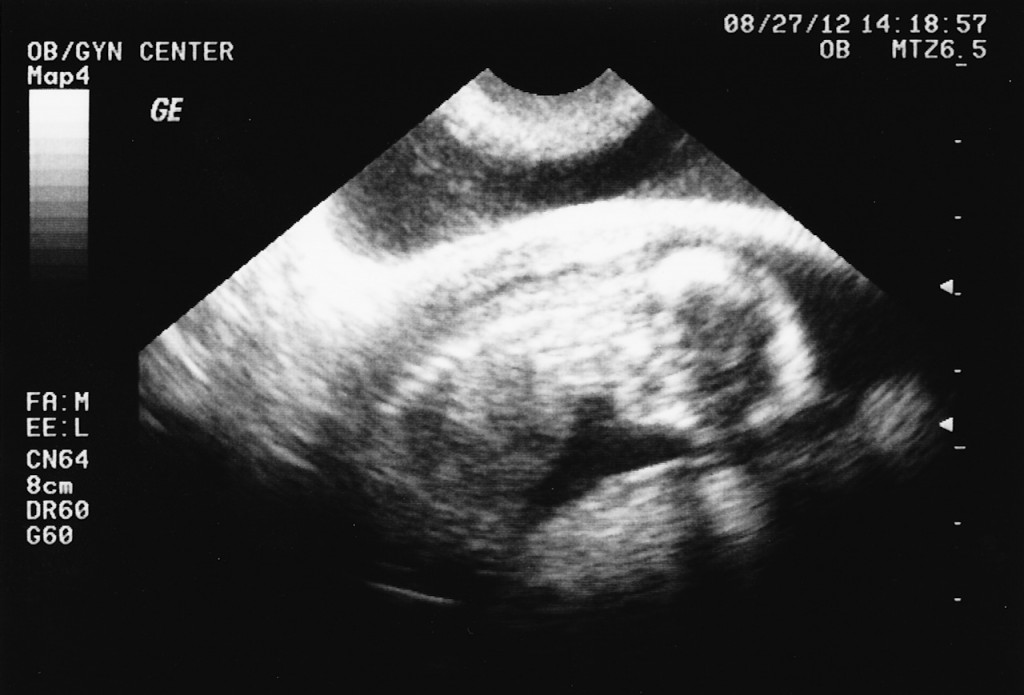

Categories events firsts First Ultrasounds! 14 Weeks. Post author By sean Post date August 27, 2012 The first ultrasounds. We thought we were ~8 weeks along, but it really is closer to 14 weeks! Tags girl, ultrasounds